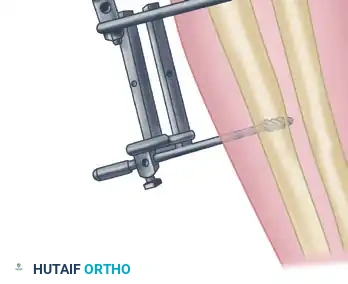

2. Hinged External Fixation

Many contemporary orthopedic surgeons prefer the application of a hinged external fixator. Although technically more complex and resource-intensive, a hinged fixator maintains concentric joint reduction while allowing immediate, guided range of motion. This theoretically improves cartilage nutrition, reduces intra-articular adhesion formation, and optimizes functional results.

Surgical Pitfall: The axis of the hinged external fixator must perfectly align with the anatomical axis of elbow rotation (passing through the center of the capitellum and the anteroinferior aspect of the medial epicondyle). Malalignment will lead to eccentric loading, subluxation, and rapid pin loosening.